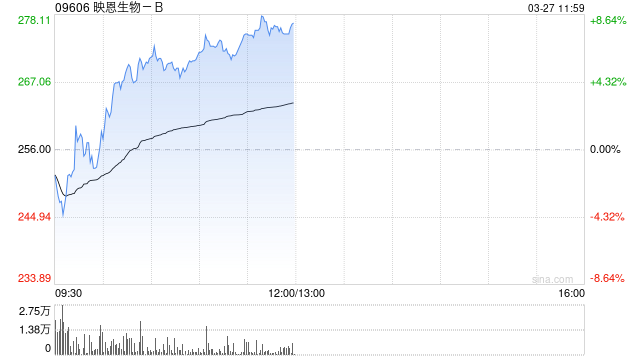

中金发布研报称,基于DCF模型,维持映恩生物-B(09606)跑赢行业评级和目标价430港元不变,较当前股价有63.4%的上行空间。公司公布2025收入18.5亿元,超该行预期,主要由于研发合作报销收入超预期。